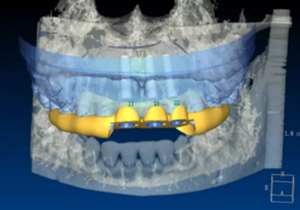

(1)術(shù)前準(zhǔn)備。拍攝臨床照片、拍攝輕開口位CBCT(NewTom)、取聚醚印模灌制超硬石膏模型。 構(gòu)建數(shù)字化模型并設(shè)計修復(fù)體:將超硬石膏模型在口外掃描(Identica? Hybrid),獲取軟硬組織表面形態(tài),構(gòu)建數(shù)字化模型,確認(rèn)咬合情況。根據(jù) 天然牙殘根頸部形態(tài)設(shè)計修復(fù)體頸部形態(tài),使修復(fù)體頸緣輪廓與原有天然牙 一致;按正常牙弓弧度與覆 、覆蓋關(guān)系,結(jié)合紅白美學(xué)等原則確定修復(fù)體 的三維形態(tài)。最后,導(dǎo)入患者面部照片,確認(rèn)模擬修復(fù)效果。 設(shè)計種植體位置并制作多級導(dǎo)板:利用Segma設(shè)計軟件,將CBCT數(shù)據(jù) 和模型掃描數(shù)據(jù)進(jìn)行配準(zhǔn),調(diào)入模擬修復(fù)效果數(shù)據(jù),以修復(fù)為導(dǎo)向設(shè)計種植 方案,設(shè)計種植體螺絲孔開口從修復(fù)體舌窩處穿出,最終實現(xiàn)螺絲固位的一 體化基臺冠修復(fù)。根據(jù)種植體信息設(shè)計多級導(dǎo)板,參考修復(fù)體形態(tài)設(shè)計導(dǎo)板 植入?yún)^(qū)頸緣外形,打印生成種植導(dǎo)板(Segma),并安裝金屬引導(dǎo)環(huán)。 設(shè)計并制作臨時修復(fù)體:如前所述,按照美學(xué)效果和咬合關(guān)系設(shè)計臨 時冠外形,頸部形態(tài)與模型齦緣輪廓一致,保證臨時修復(fù)體在術(shù)后可以封閉 拔牙窩。3顆臨時冠為連冠,齦外展隙適當(dāng)加大,為術(shù)后軟組織生長提供一 定的空間。在臨時冠近兩側(cè)鄰牙的切角處預(yù)留翼板,保證臨時冠戴入時可以 找到準(zhǔn)確的位置。以銑削的方式加工臨時冠(Segma),待種植體植入后 將其在口內(nèi)粘接于臨時基臺上。

圖5 設(shè)計種植體位置與多級導(dǎo)板